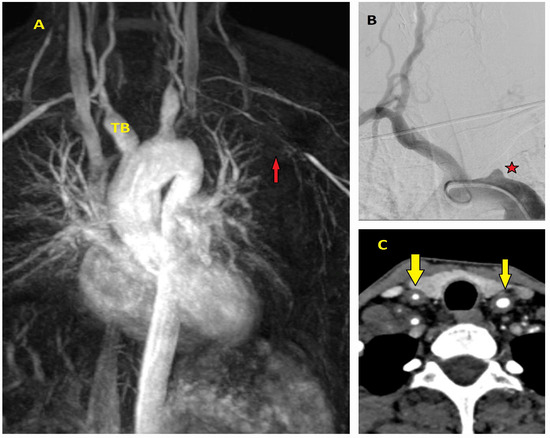

5.2.4. Magnetic Resonance Imaging (MRI)

- Evangelista, A.; Sitges, M.; Jondeau, G.; Nijveldt, R.; Pepi, M.; Cuellar, H.; Pontone, G.; Bossone, E.; Groenink, M.; Dweck, M.R.; et al. Multimodality imaging in thoracic aortic diseases: A clinical consensus statement from the European Association of Cardiovascular Imaging and the European Society of Cardiology working group on aorta and peripheral vascular diseases. Eur. Heart J. Cardiovasc. Imaging 2023, 24, e65–e85. [Google Scholar] [CrossRef] [PubMed]

- Bossone, E.; Czerny, M.; Lerakis, S.; Rodríguez-Palomares, J.; Kukar, N.; Ranieri, B.; Russo, V.; Punzo, B.; Cocchia, R.; Cademartiri, F.; et al. Imaging and Biomarkers in Acute Aortic Syndromes: Diagnostic and Prognostic Implications. Curr. Probl. Cardiol. 2021, 46, 100654. [Google Scholar] [CrossRef]